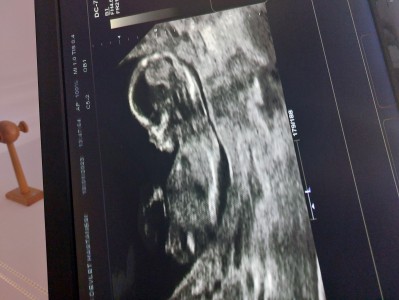

Anlayan varmı? Bakar misiniz

kızlar bakar mısınız cinsiyet tahmini

15+0

Masallah haftasi da bayağı ileride doktoe göremedi mi acaba. Ben 13+2 de ultrasona girer girmez pipiyi gördüm. Doktor da maşallah şahin gibi gozlerin var demişti. Sizin ki kiz olmasin

Sanki kız gibi haftasına göre soylemesi lazımdı doktorun